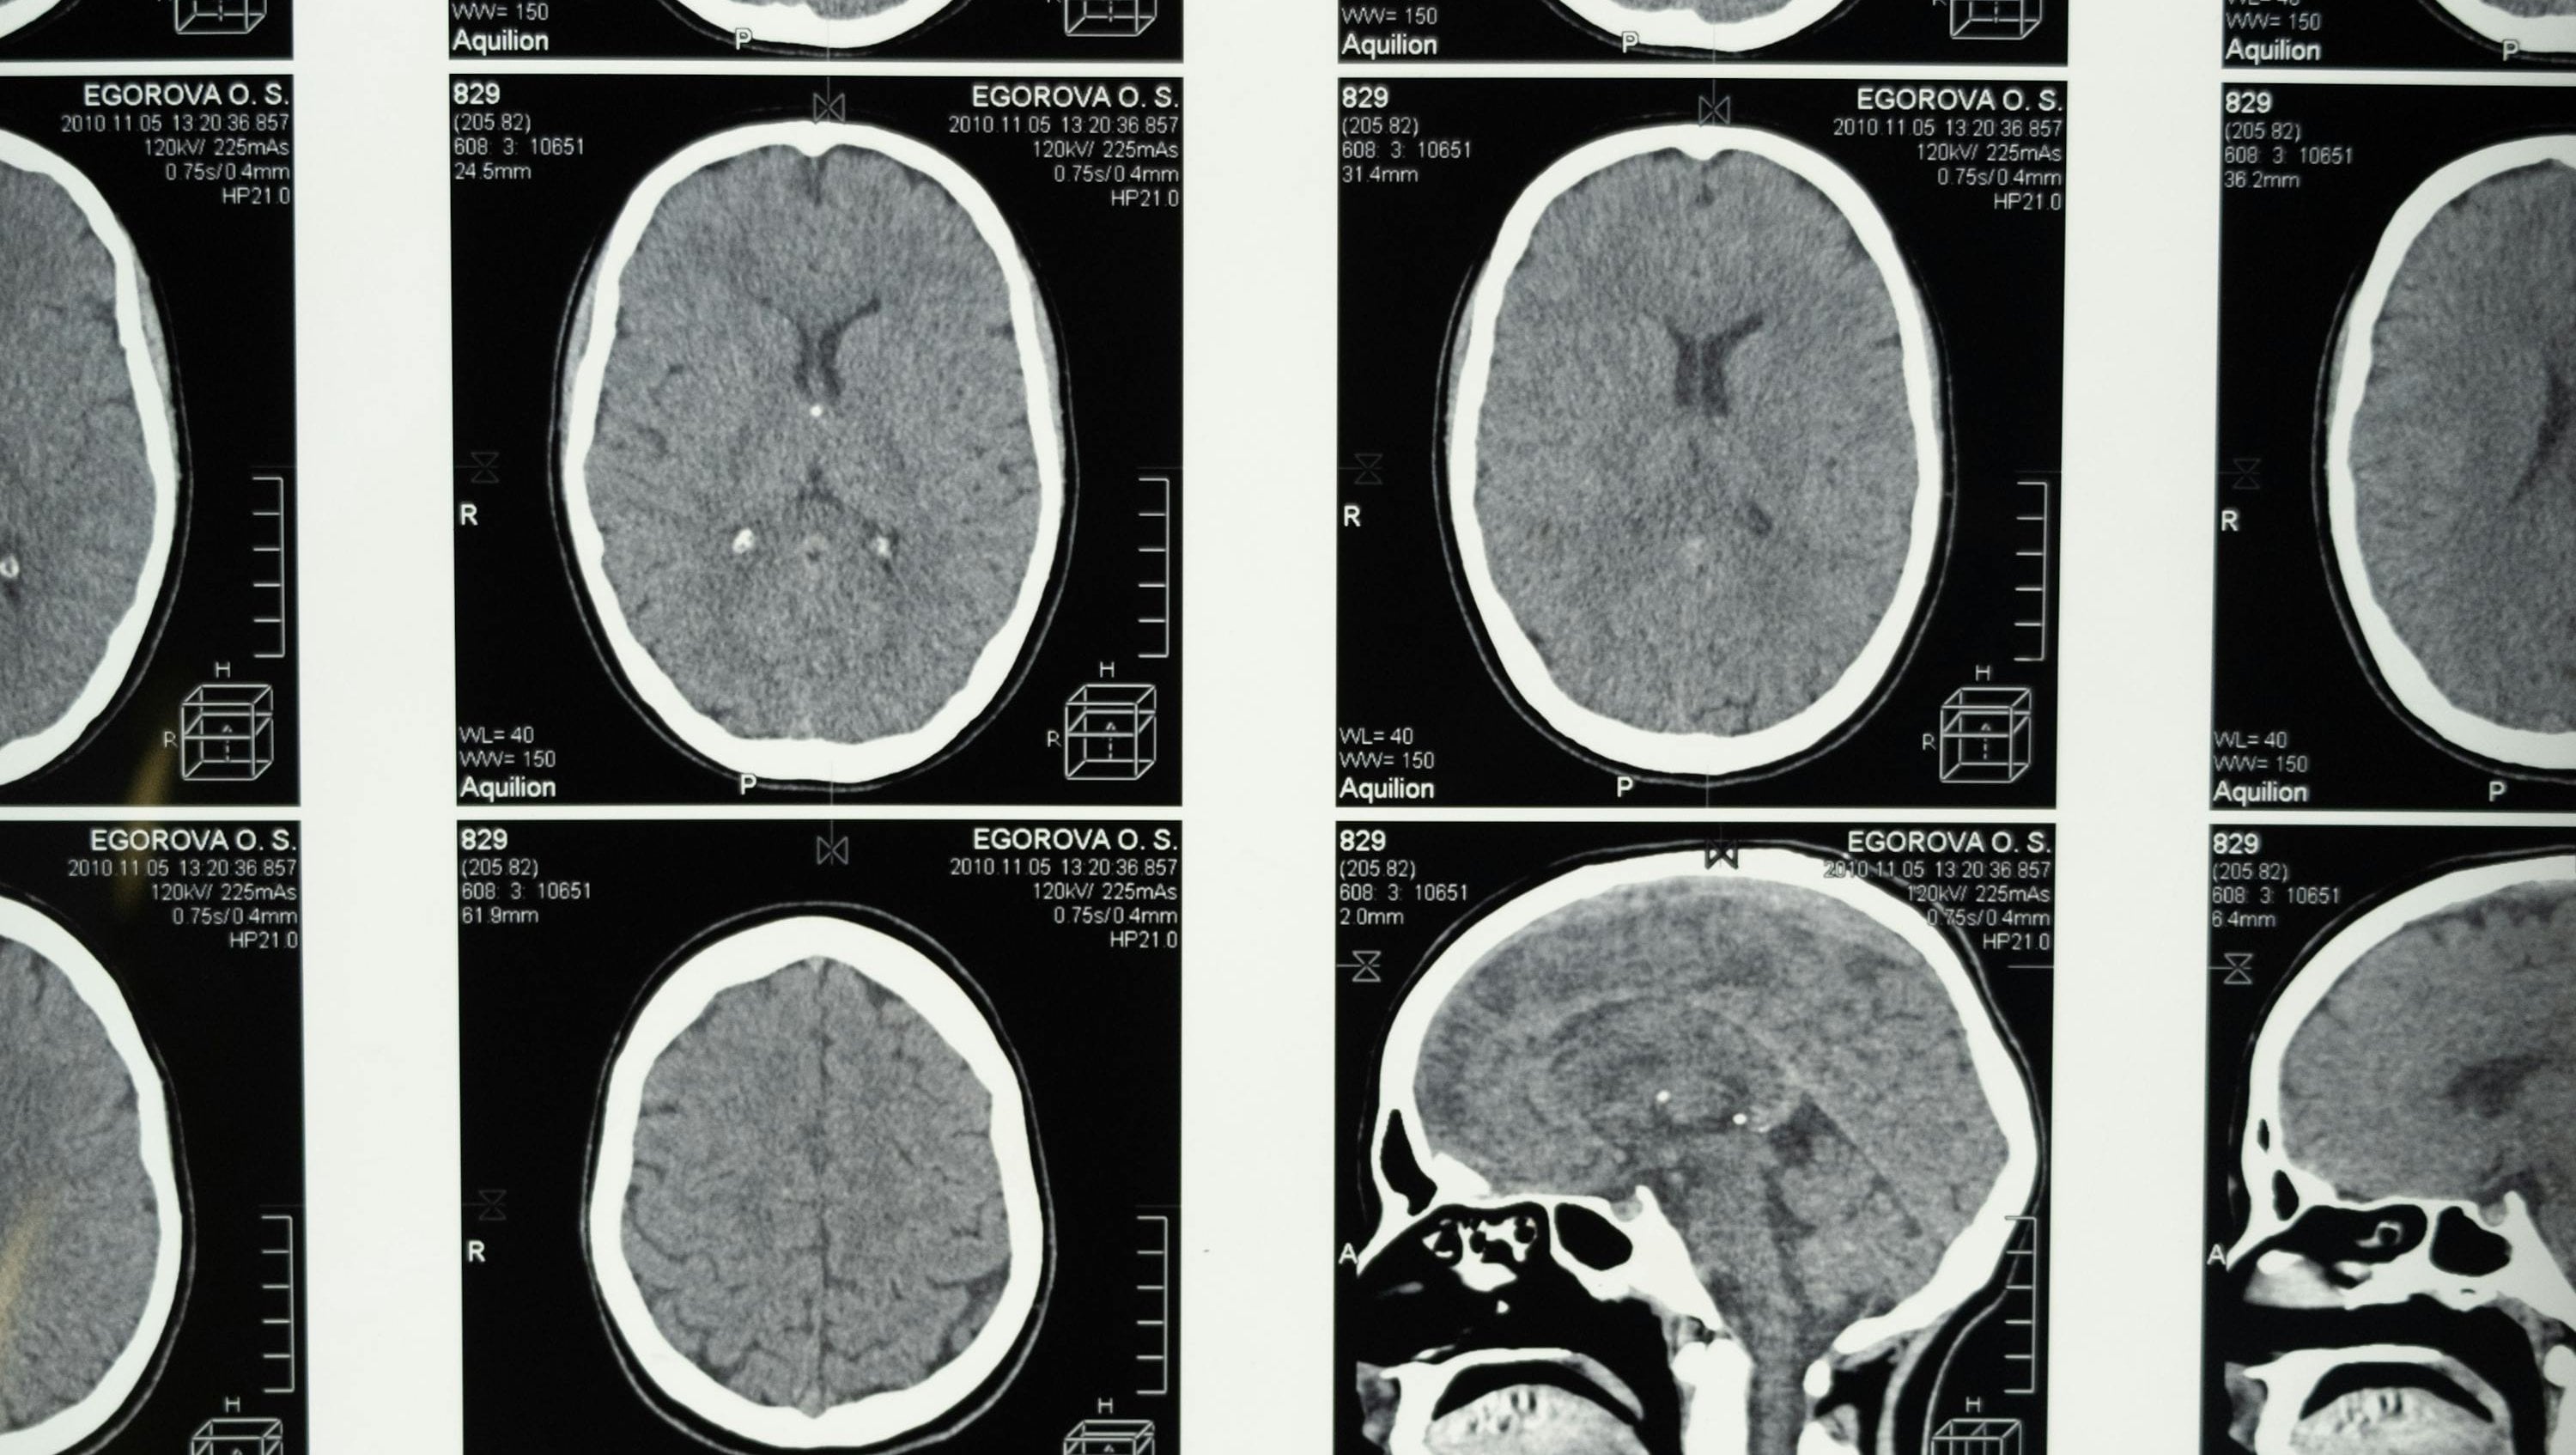

Beyin, insan bedeninin en karmaşık ve en hayati organlarından biridir. Tüm bilinç süreçlerimizi, motor fonksiyonlarımızı ve duygusal tepkilerimizi yöneten bu organ, tarih boyunca sayısız bilimsel araştırmanın odak noktası olmuştur. Ancak, beyin cerrahisinde gerçekleştirilen bazı operasyonlar vardır ki, duyduğunuzda inanması güç gelebilir. Bunlardan en şaşırtıcı olanı, hemispherektomi adı verilen cerrahi işlemdir.

Hemispherektomi, beynin bir yarısının tamamen çıkarılması veya işlevsiz hâle getirilmesini içeren bir ameliyattır. Daha da ilginci, bu operasyonu geçiren bazı hastalar, büyük ölçüde normal yaşamlarını sürdürebilmekte, hatta bilişsel ve motor fonksiyonlarının büyük kısmını koruyabilmektedir. Peki, beynin yarısı olmadan yaşamak nasıl mümkün olabiliyor? Bu makalede, bu olağanüstü cerrahi işlemin arkasındaki bilimsel gerçekleri inceleyeceğiz.

Hemispherektomi, ilk olarak 20. yüzyılın ortalarında geliştirilmiş ve genellikle şiddetli epilepsi vakalarında kullanılan bir cerrahi tekniktir. Özellikle, tek bir beyin yarımküresini etkileyen ve diğer tedavi yöntemlerine yanıt vermeyen hastalarda uygulanır. Bu operasyonun amacı, beynin bir yarısındaki aşırı elektriksel aktiviteyi tamamen ortadan kaldırarak hastanın nöbetlerini durdurmaktır.

Beynin Yarısı Alındığında Ne Olur?

Beynin iki yarımküresi birbirinden farklı görevler üstlenir. Genellikle sol yarımküre, dili işleme ve mantıklı düşünme becerileriyle ilişkilidirken, sağ yarımküre daha çok uzamsal farkındalık, yaratıcılık ve sezgisel düşünce süreçlerinden sorumludur.